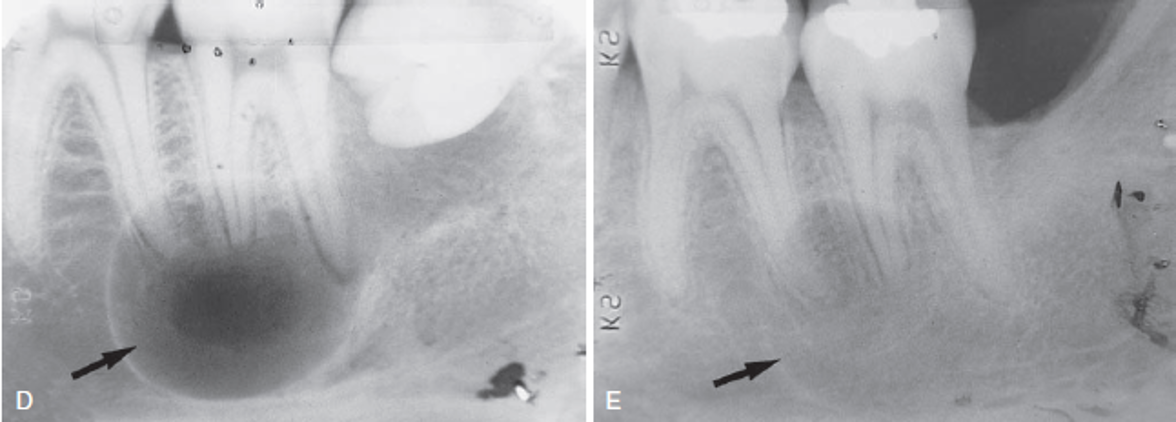

This unilocular radiolucency around the crown of an unerupted second premolar is most likely a

A) normal developmental sac.

B) dentigerous cyst.

C) primordial cyst.

D) lateral periodontal cyst.

A dentigerous cyst is a well-defined unilocular radiolucency around the crown of an unerupted tooth. A normal developmental sac has a much smaller radiolucency around the crown. A primordial cyst develops in place of a tooth. The lateral periodontal cyst is most often seen in the mandibular cuspid and premolar region.